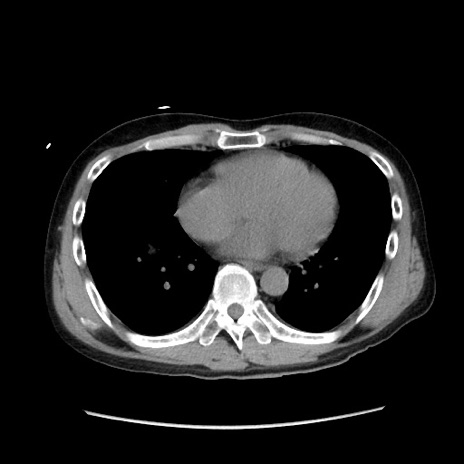

冠状断像